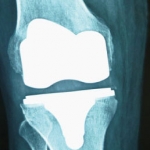

RX: proyección anteroposterior de PTR Medial Pivot